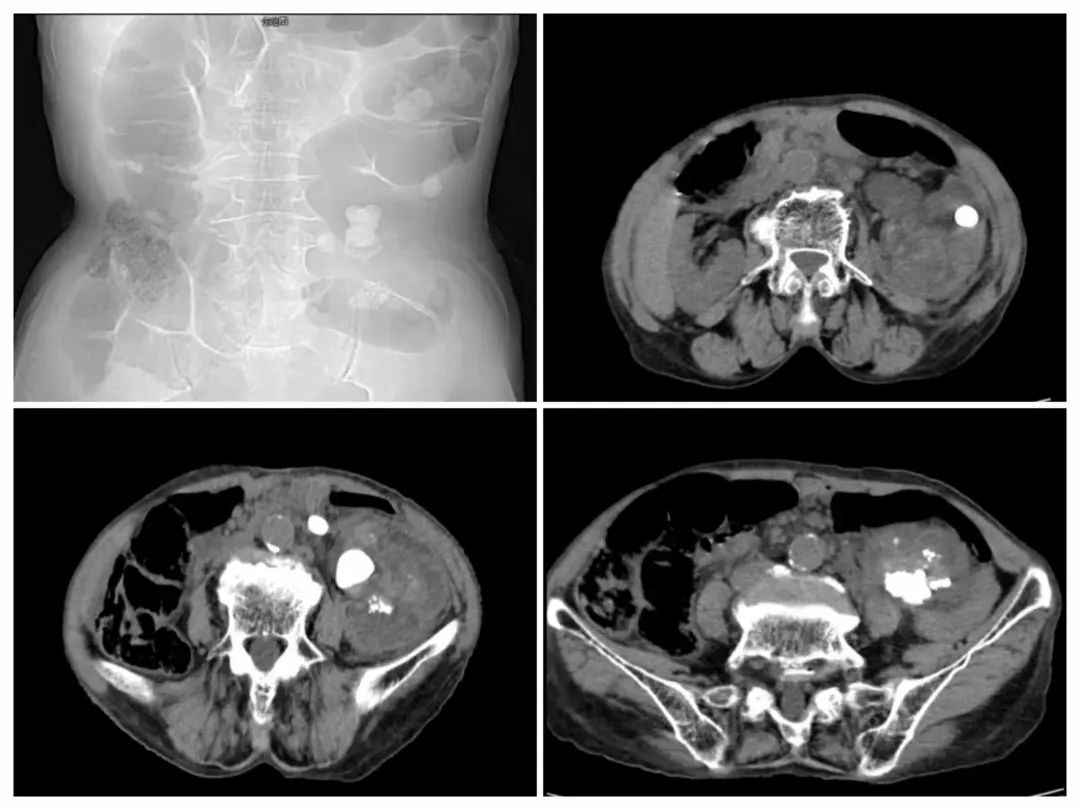

影像学检查

患者在完善相关检查后送手术室由黄河主任主刀,在局麻下行经皮左肾穿刺造瘘术。术程顺利,术后穿刺液培养结果显示为大肠埃希菌感染。患者术后7天复查,情况逐渐好转,生命体征趋于平稳。然而,由于患者年事已高,家属对于进一步的经皮肾镜取石术治疗心存顾虑,并要求拔除引流管,我科医生充分沟通无果后,予以拔除。此后半年间,患者虽经保守治疗,但结石问题始终未能得到根本解决,反复感染成为家常便饭。